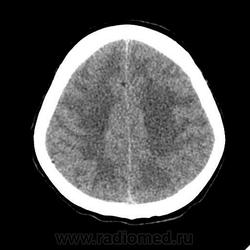

КТ головного мозга, кровоизлияние.

"Скорая" привезла женщину 75 лет, найденную на улице. На КТ направлена с д-зом: кома неясного происхождения. Вот такая картина на КТ.

PS. Не очень понял про ///отек мозга///, есть снижение плотности (отек и ишемия) белого вещества левого полушария и задних отделов правого.

Про отек: субарахноидальных щелей совсем нет, по белому веществу и в стволе снижение плотности, извилины утолщены, серое вещество на этом фоне выглядит более светлым, толстым, подушкообразным.

Причина таких кровоизлияний, как правило, гипертензия и атеросклероз.